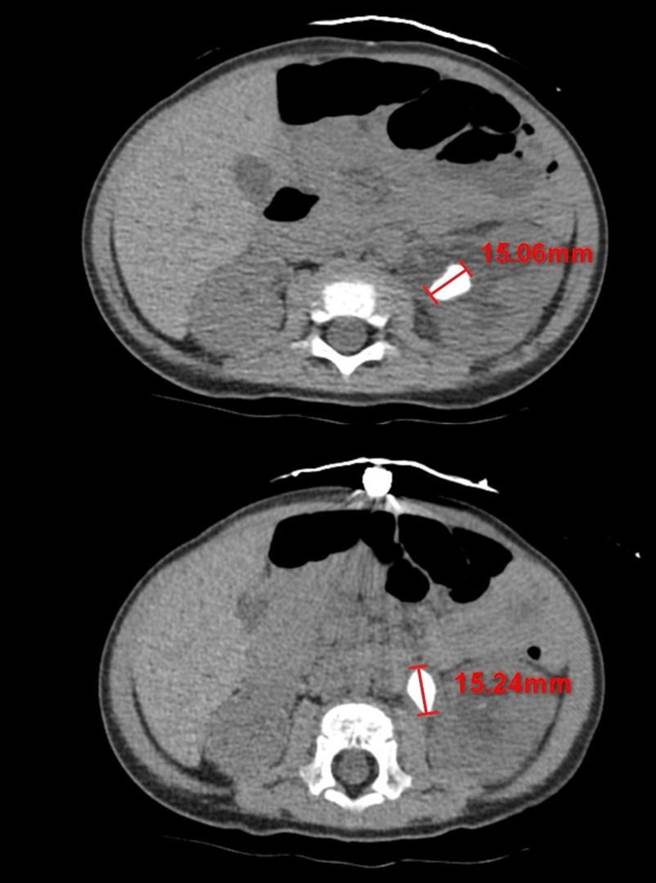

花蓮年僅11個月大余姓男嬰體內長出2顆約1.5公分的腎結石,造成急性腎臟發炎,經花蓮慈濟醫院醫護團隊使用全院最小尺寸的腎臟鏡,以「經皮腎鏡取石手術」順利將腎結石夾出後,已康復出院。(花蓮慈濟醫院提供/羅亦晽花蓮傳真)

花蓮一名年僅11個月大余姓男嬰體內長出2顆約1.5公分的腎結石,造成急性腎臟發炎,由於男嬰輸尿管直徑僅0.1公分,尚未發育完全,即便儀器震碎石頭恐無法順利排出,經花蓮慈濟醫院醫護團隊使用全院最小尺寸的腎臟鏡,以「經皮腎鏡取石手術」順利將腎結石夾出,男嬰已康復出院。慈院表示,此次病例查找文獻資料十分罕見,是院史年紀最小的腎結石取出手術。

余姓男嬰今年3、4月曾因泌尿道感染發燒到其他醫院治療,透過藥物控制狀況,沒想到7月再度發燒,被家人送到花蓮慈濟醫院就醫且照腎臟超音波才發現其腎臟裡有2顆約1.5公分大的結石,其中1顆還堵在輸尿管與腎臟的銜接處,造成堵塞與腎水腫。